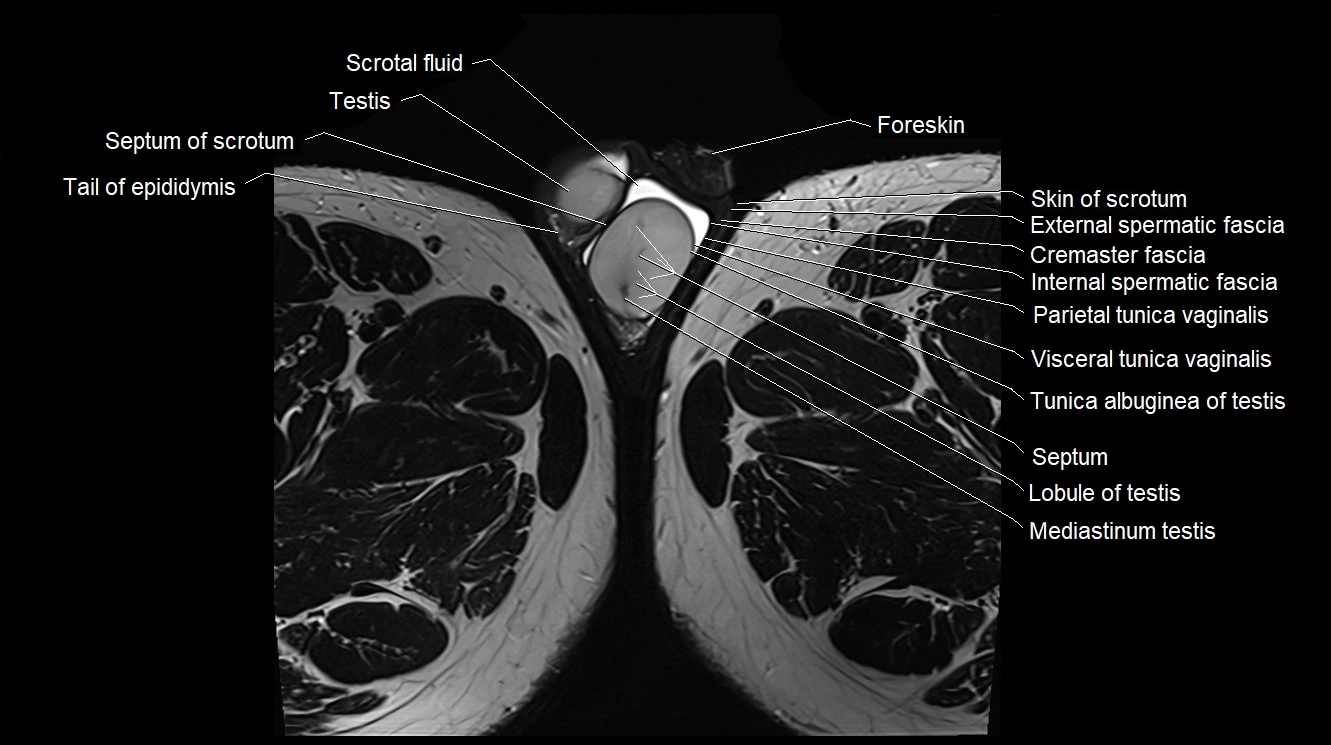

- Cremaster fascia

- External spermatic fascia

- Internal spermatic fascia

- Lobule of testis

- Mediastinum testis

- Parietal tunica vaginalis

- Scrotal fluid

- Septum of scrotum

- Septum of testis

- Skin of scrotum

- Tail of epididymis

- Testis

- Tunica albuginea of testis

- Visceral tunica vaginalis